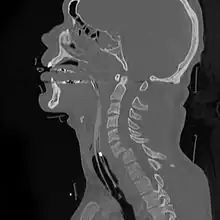

A cervical fracture, commonly called a broken neck, is a fracture of any of the seven cervical vertebrae in the neck. Examples of common causes in humans are traffic collisions and diving into shallow water. Abnormal movement of neck bones or pieces of bone can cause a spinal cord injury, resulting in loss of sensation, paralysis, or usually death soon thereafter (~1 min.), primarily via compromising neurological supply to the respiratory muscles and innervation to the heart.